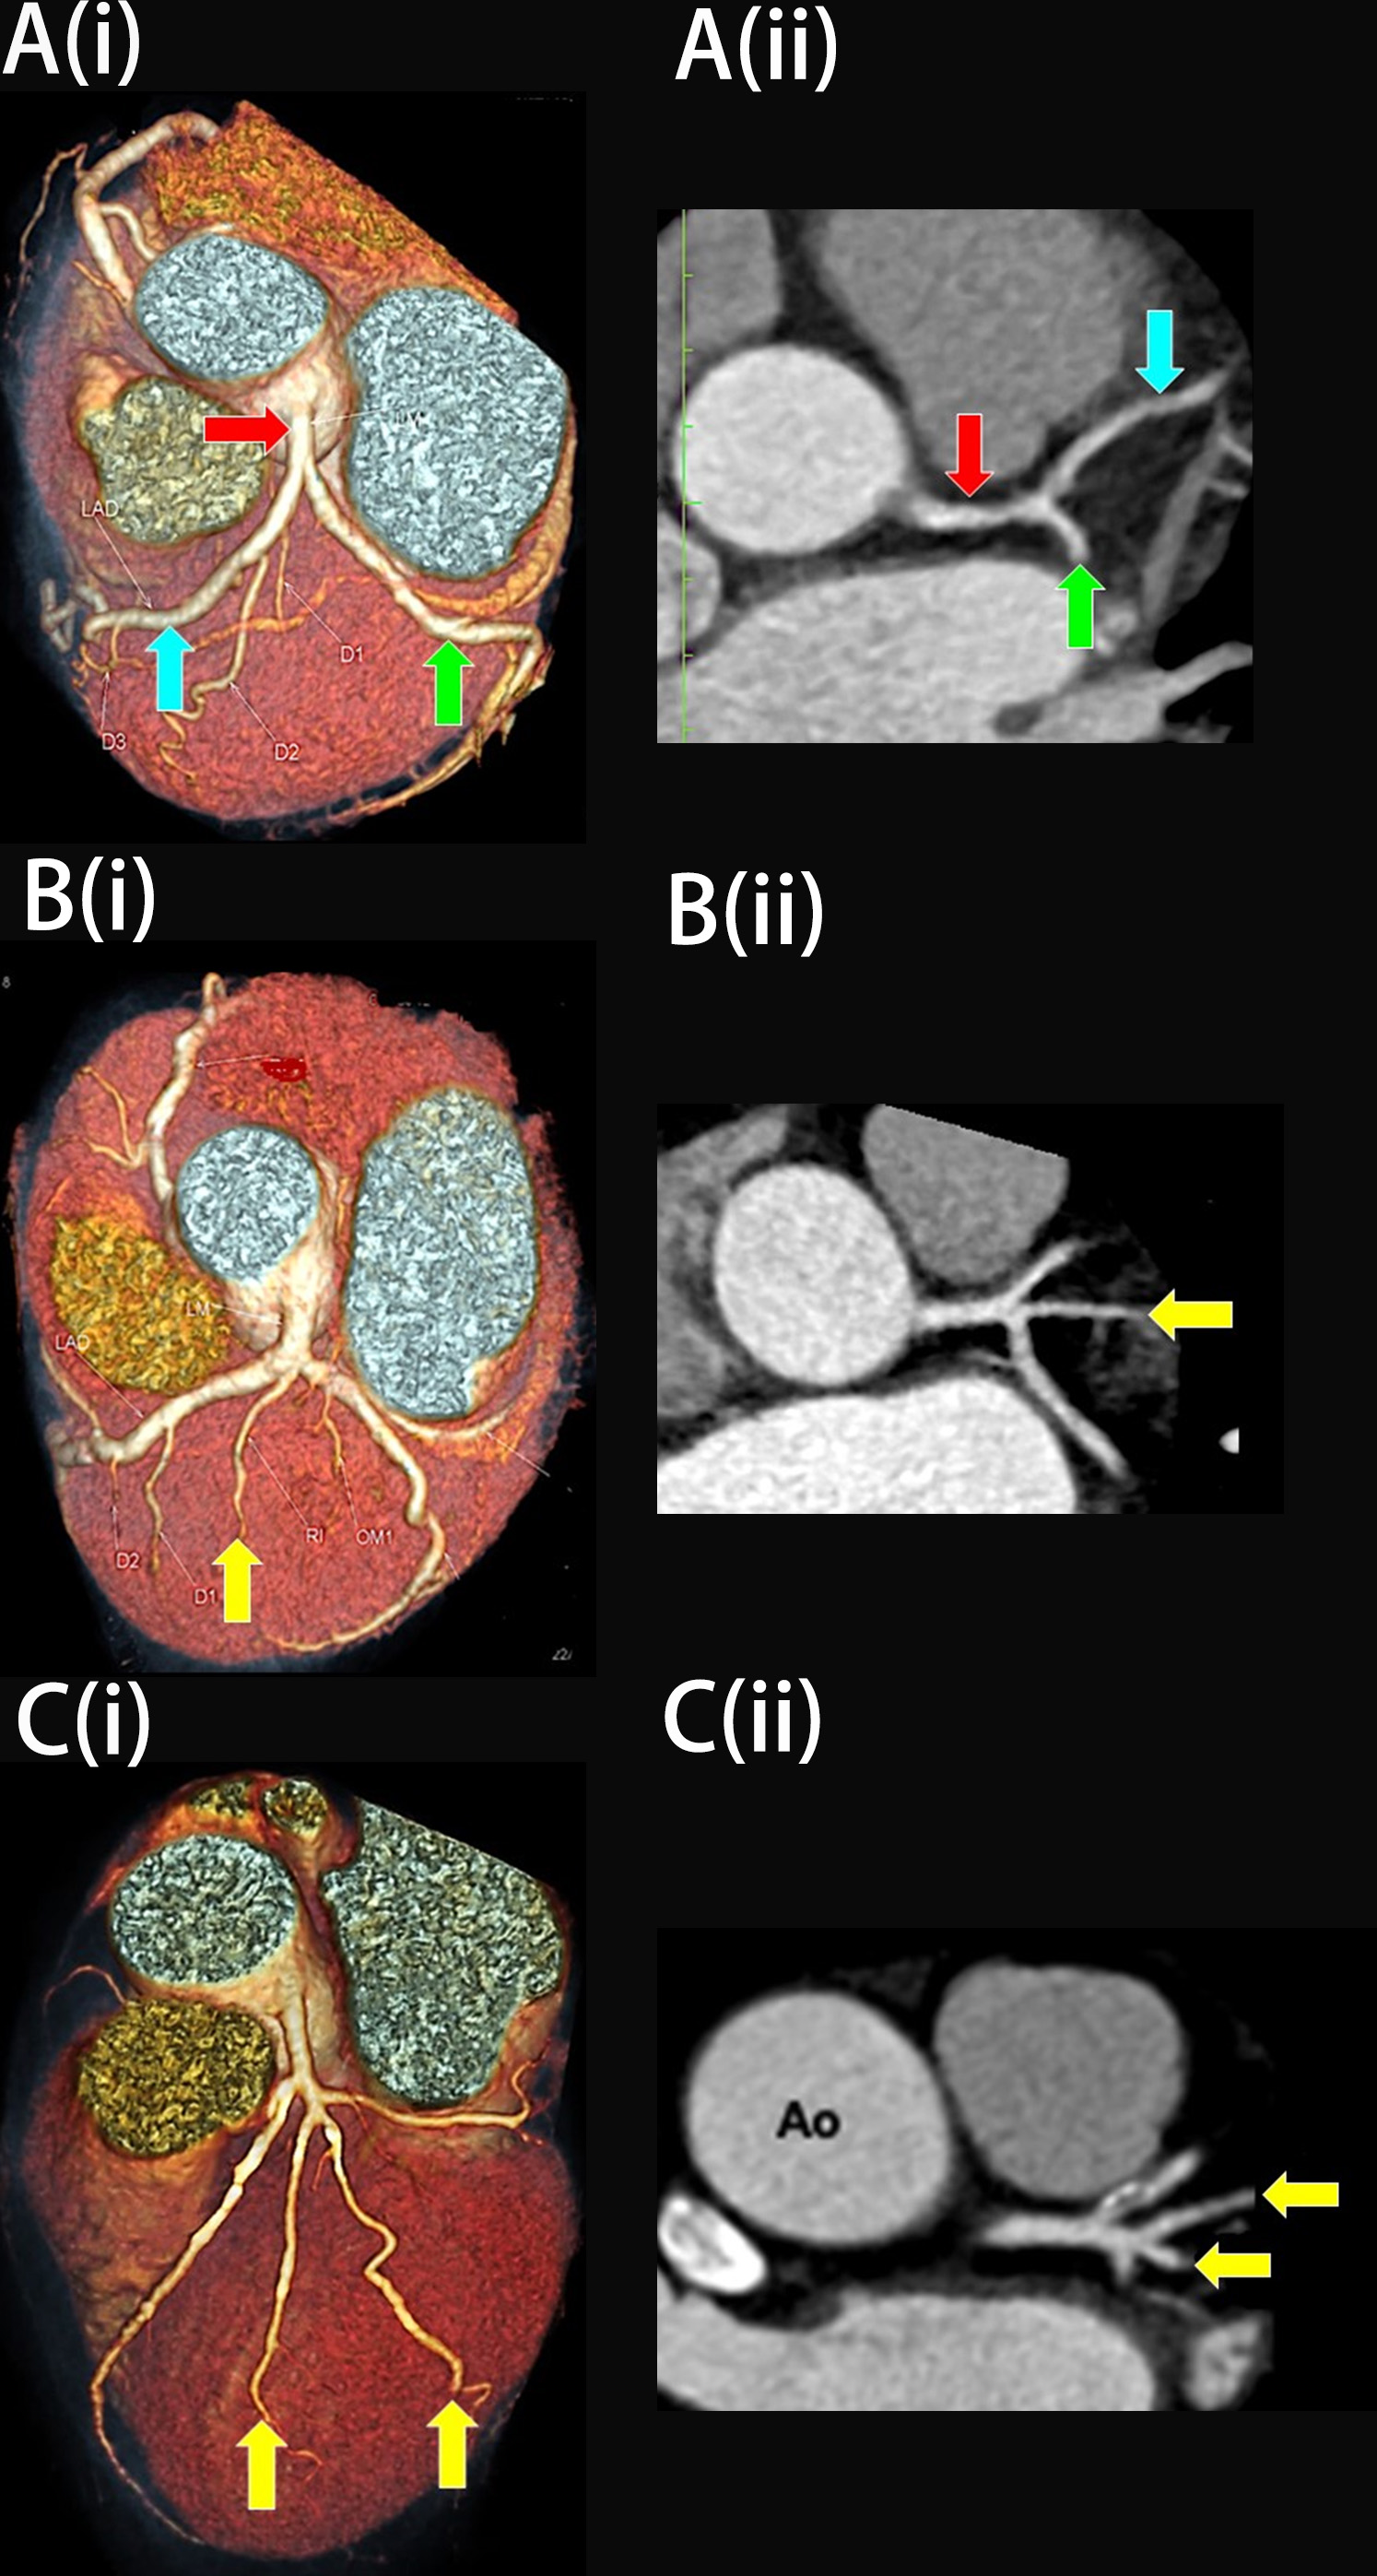

This study comprised of 139 females with low cardiovascular risk and no history of any cardiovascular diseases. Their ages were between 21 to 60. The findings revealed that 66.2% (n = 92) of the study participants had no aberrant RI artery at the LBR (Fig. 5A), while the remaining 33.8% (n = 47) had an RI (Fig. 1, and Fig. 6A,C). When present, the RI arteries were either in a single (30.2%, n = 42, Fig. 5B) or double vessel configurations (3.6%, n = 5, Fig. 5C). The inter-rater kappa for RI identification using MPR images was 1.0, demonstrating a very good agreement between the two investigators.

Fig. 5. The three variations of the left main bifurcation angle in cardiac computed tomography angiography images viewed in (i) Three-dimension volume rendering technique and (ii) Multiplanar reconstruction of the left bifurcation region (axial view). (A) Bifurcation. (B) Trifurcation with one single ramus intermedius (RI). (C) Quadfurcation with two vessels of RI. The red arrow indicates the left main coronary artery, the blue arrow indicates the left anterior descending artery, the green arrow indicates the left circumflex artery, and the yellow arrow indicates RI. Ao, Aorta.